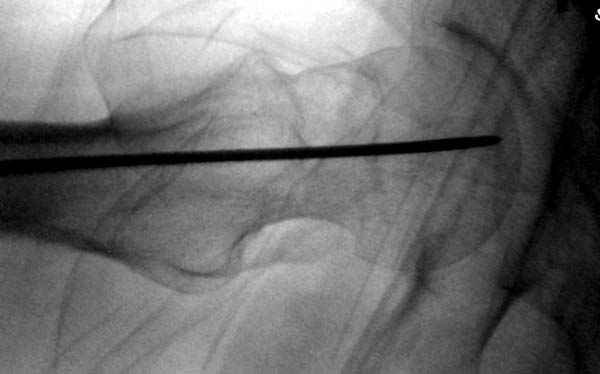

Re: неполный перелом шейки

Профилактику дальнейшего раскола неполного перелома шейки провели тремя канюлированными шурупами.

На второй день после выписки упал дома. Снимки приложены. Коллеги рекомендуют удаление шурупа и вытяжение. Что делать?